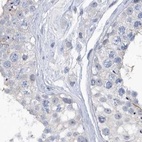

Immunohistochemistry analysis in human cerebral cortex and pancreas tissues using Anti-SRGAP3 antibody. Corresponding SRGAP3 RNA-seq data are presented for the same tissues.